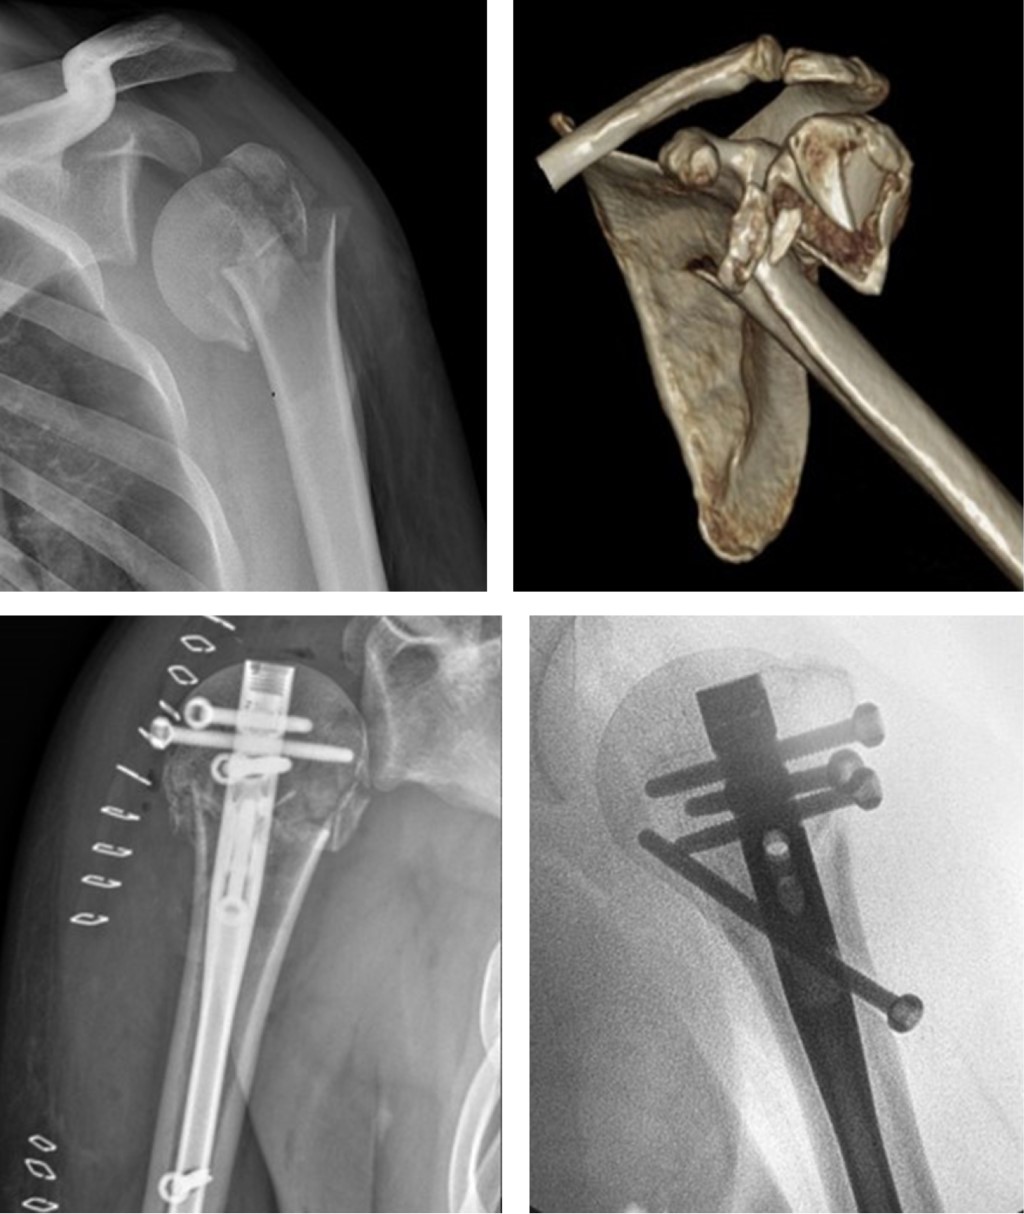

Introduction: The development of orthopedic surgery has led to a constant production of new implants. Simulation is a key tool in the use of new implants in orthopedic surgery. Objective: To describe in detail the ideal transfer process from the new implant instructions "brochure" to direct application to a patient through a "boot camp". Material and methods: A work modality are proposed for the reception of new orthopedic and trauma implants based on the "boot camp" modality. The objective is to carry out a process of theoretical analysis of the implant, leading to simulation in artificial bones and joints, and finally, to the cadaveric laboratory practice. Results: A pilot experience of this work modality is described in relation to a real clinical case for the application of a new implant for proximal humerus fractures called AFFIXUS® Natural Nail® from the company BIOMET®. Conclusions: This "boot camp" is a safe way to obtain specific technical skills of orthopedic surgery, without putting surgeons or patients at risk. The fact of establishing a structured system for the evaluation of new implants in orthopedics and traumatology is novel.

Figure 1

Figure 2

Figure 3

Figure 4